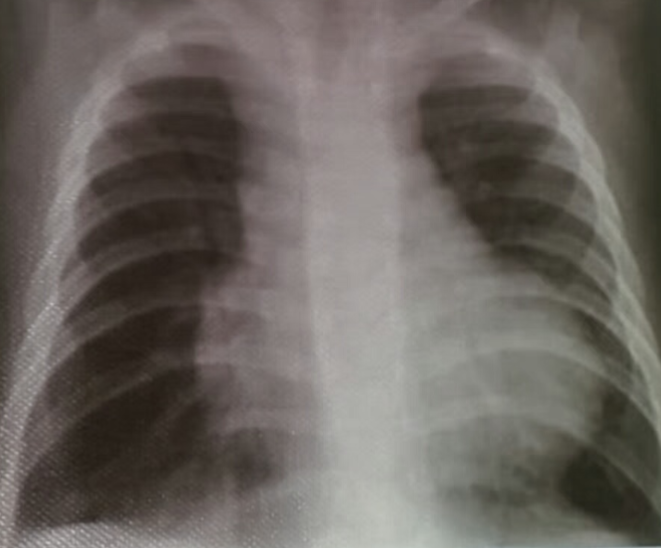

- AP chest film which shows opacification of the middle and lower zones of - (1 .the left lung. The upper border of the opacity is concave

- .This indicates pleural effusion (PE) - (2

- After inserting chest tube, pus was coming out. This means that the PE is - (3 .an Empyema

- .The cause of this empyema is most likely a Bacterial Pneumonia - (4

- The age of the patient is an 8 years which means that the most likely - (5 .organism is Streptococcus Pneumonae